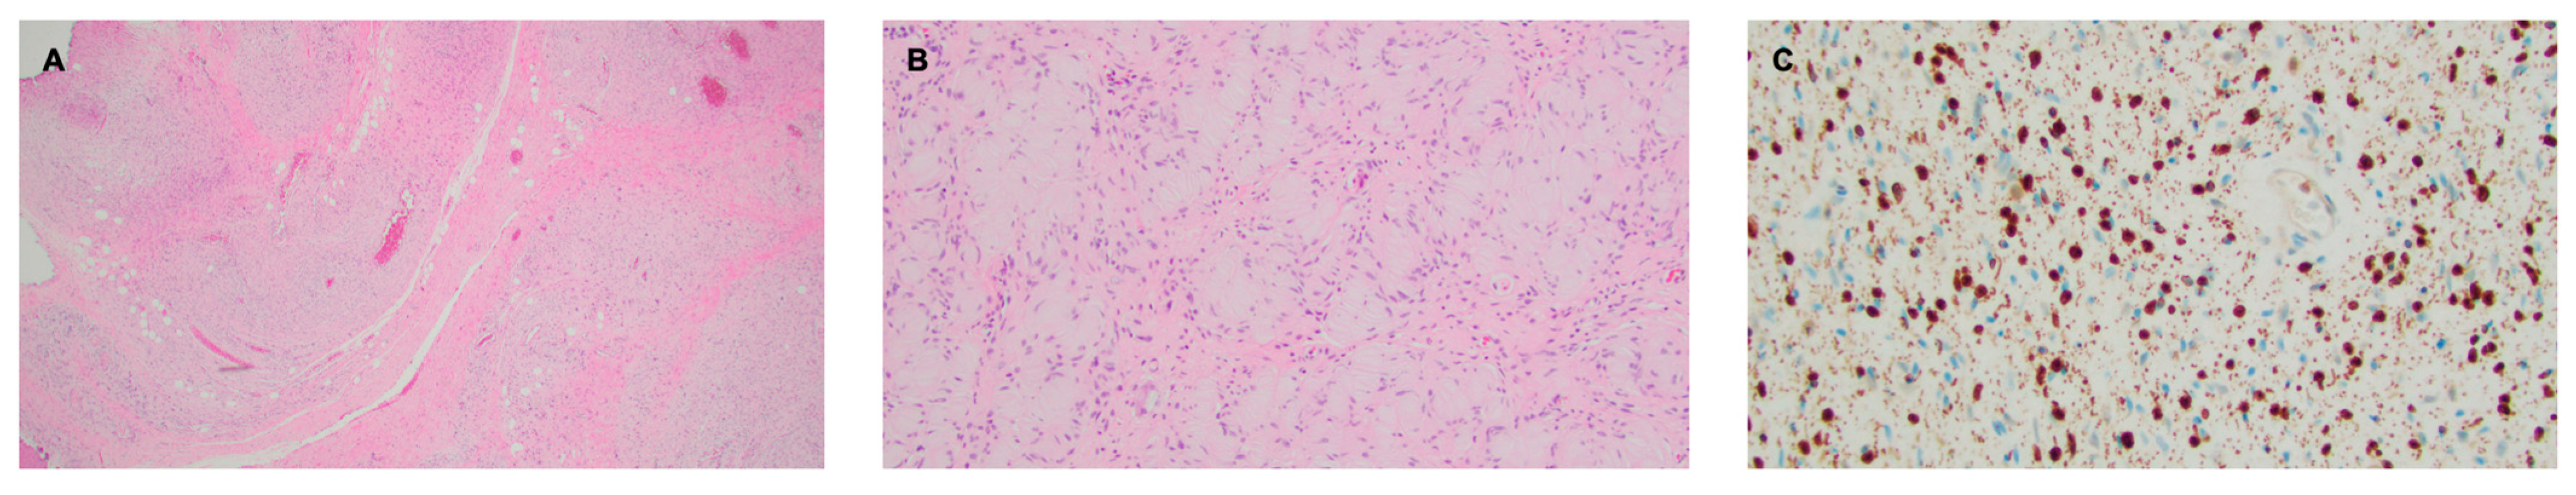

Figure 3.

Right facial plexiform neurofibroma. (A) H&E stain, 2× objective, highlighting a diffusely infiltrative proliferation of spindled to ovoid cells with loose collagenous stroma. A vague bundled and tortuous pattern is visible at this power. (B) H&E stain, 10× objective, demonstrating an area featuring abundant pesudo-Meissner corpuscles, a feature frequently encountered in diffuse and plexiform neurofibromas. (C) S100 stain, 20× objective, showing nuclear and granular cytoplasmic staining, as compared to the diffuse staining seen in schwannomas.